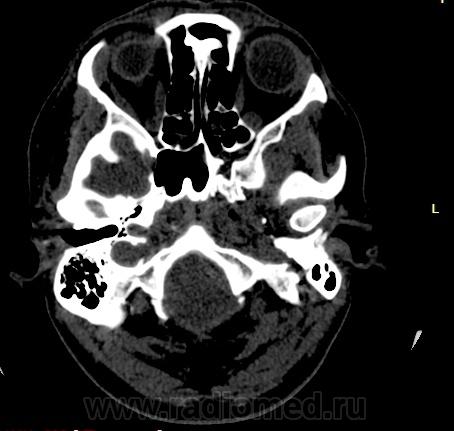

Прошу разрешить спор. По КТ - норма. Женщина, 1967г.р., жалобы на головную боль, больше в затылочной области. По-моему, не КТ-шное это дело но всеж...

Открыл. В мозгу ничего осбенного не увидел. По поводу Киари ничего не скажу, на аксиалах не вижу, а реконструкции эти срезы не строят Да и отношусь я к этой патологиии как к норме.

Аномалию Арнольда-Киари 1типа.

На МРТ выставили  аномалию Арнольда-Киари 1, нам сказали фу... На что я ответил, что по " ловцу и рыба". Во - первых, линию на КТ провести сложно ( в данном иссл.), во-вторых - естественные артефакты костей основания. И вообще пошли на...МРТ! Но осадок остался.

Для Арнольда-Киари I МРТ - как раз и есть метод диагностики, а на КТ это дело можно лишь заподозрить. Плюньте на осадок. Ну хотите, я плюну?) Тока отойдите, а то разъест))).